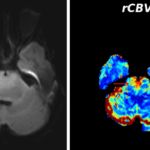

- Masslike area of T2/FLAIR signal hyperintensity involving the pons, midbrain including the cerebral peduncles, left eccentric medulla, and left greater than right middle cerebellar peduncles

- Corresponding faint restricted diffusion in the ventral aspect of the pons

Diffuse midline glioma